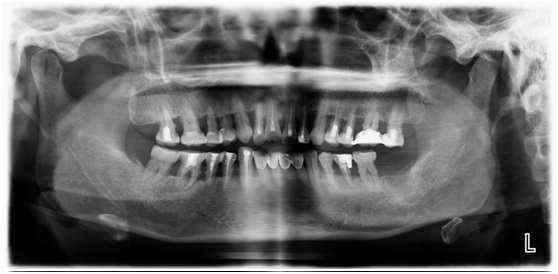

全口根管治疗术,术后效果图